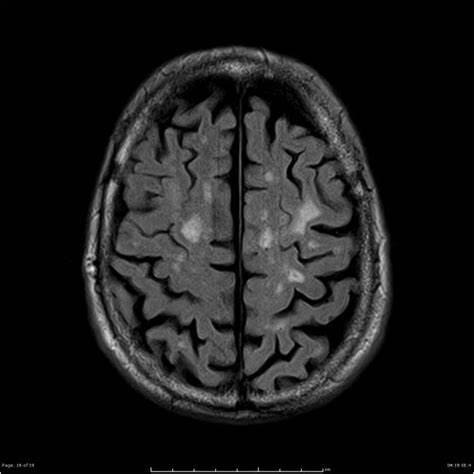

So why is this? The answer is a medical condition known as chronic traumatic encephalopathy – or CTE for short.

This is a degenerative condition – it causes brain tissue to die over a long period of time. This leads to dementia and, eventually, death as the brain loses healthy tissue and shrinks.

Either of these scenarios results in the head receiving a blow, though a much more significant one in a clash of heads. Such an impact can cause nerve cells to be damaged and die around the impact site. Repeated blows massively amplify the effect on the brain – over long periods, this damage can become so severe that large portions of the brain die, resulting in the development of CTE.

Some players at higher levels, most notably Petr Čech, choose to wear helmets designed to reduce the likelihood of suffering a serious head injury in a potential collision. Research into CTE and MND also continues in the hope that we will soon be able to better understand the condition and alleviate the risks somewhat at higher levels. Aseriesofheadscansshowingthedistributionofpressureafteraheadimpact